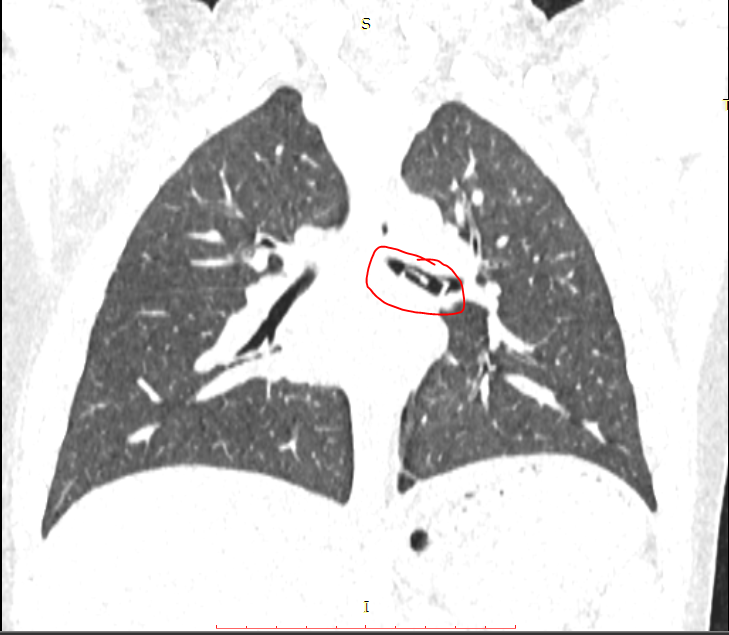

Cháu được chỉ định chụp CT ngay sau đó, trên phim CT, ghi nhận ở phế quản trái có một khối dị vật hình chữ nhật, kích thước (1x2cm). Để lấy được dị vật, bệnh nhi được chỉ định nội soi phế quản trái.

| Dị vật nằm trong phế quản cháu bé. |